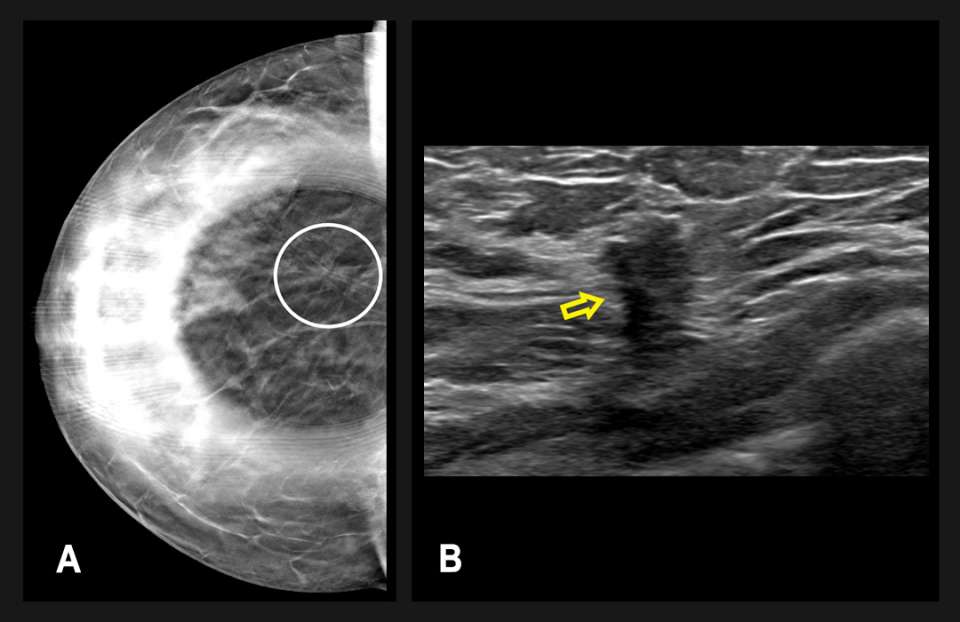

Diagnostic mammography followed one month thereafter and included spot compression views of the area of architectural distortion in the right breast (Figure 2A). Targeted breast ultrasonography showed a vague hypoechoic area measuring up to 11 mm, which correlated with the mammographic findings (Figure 2B). The finding was categorized as BI-RADS 4B, and an ultrasound-guided biopsy was recommended.